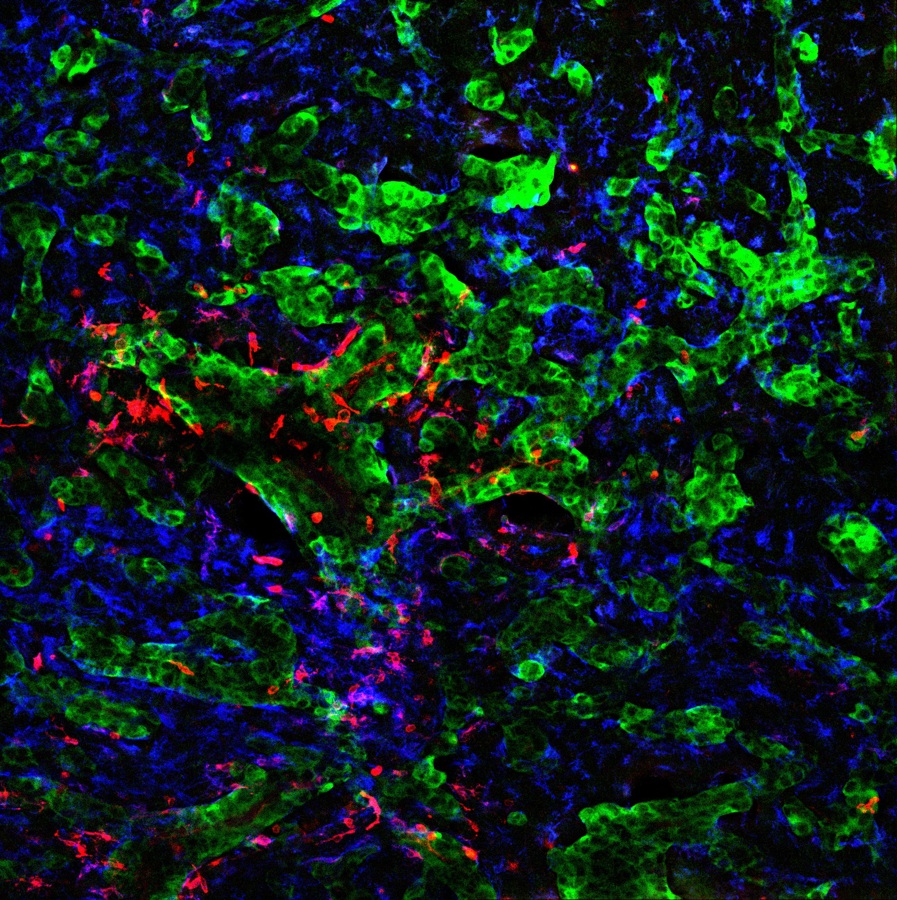

Las BCI son unas herramientas que, mediante sensores implantados en el cerebro, captan las señales eléctricas que las neuronas usan para transferir información por todo el cerebro y las convierten en acciones.